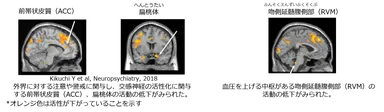

自分で自分の肌に触れると、触れる動作と心地よい感覚を脳内で統合し、ストレス状態における過剰な交感神経の活性を鎮めます。また、外部に対する注意や意識を低下させるとともに、危機感や不安感を抑制する効果も示されました。

実験では、実験参加者が自身の左手の甲を単純な動きでソフトに触れることで、脳の変化をfMRIにて測定しました。

その結果、外界に対する注意や警戒に関与し、交感神経の活性化に関与する前帯状皮質(ACC)、扁桃体の活動の低下がみられました。さらに、血圧を上げる中枢がある吻側延髄腹側部(RVM)の活動の低下も確認できています。

セルフタッチによるこのような反応は、「自分は安全な環境にいる、大丈夫」という感情に繋がると考えられます。肌にセルフタッチするスキンケアを通して安心感を得ることは、前向きな気持ちで日々を過ごせる幸福感にもつながると期待できます。